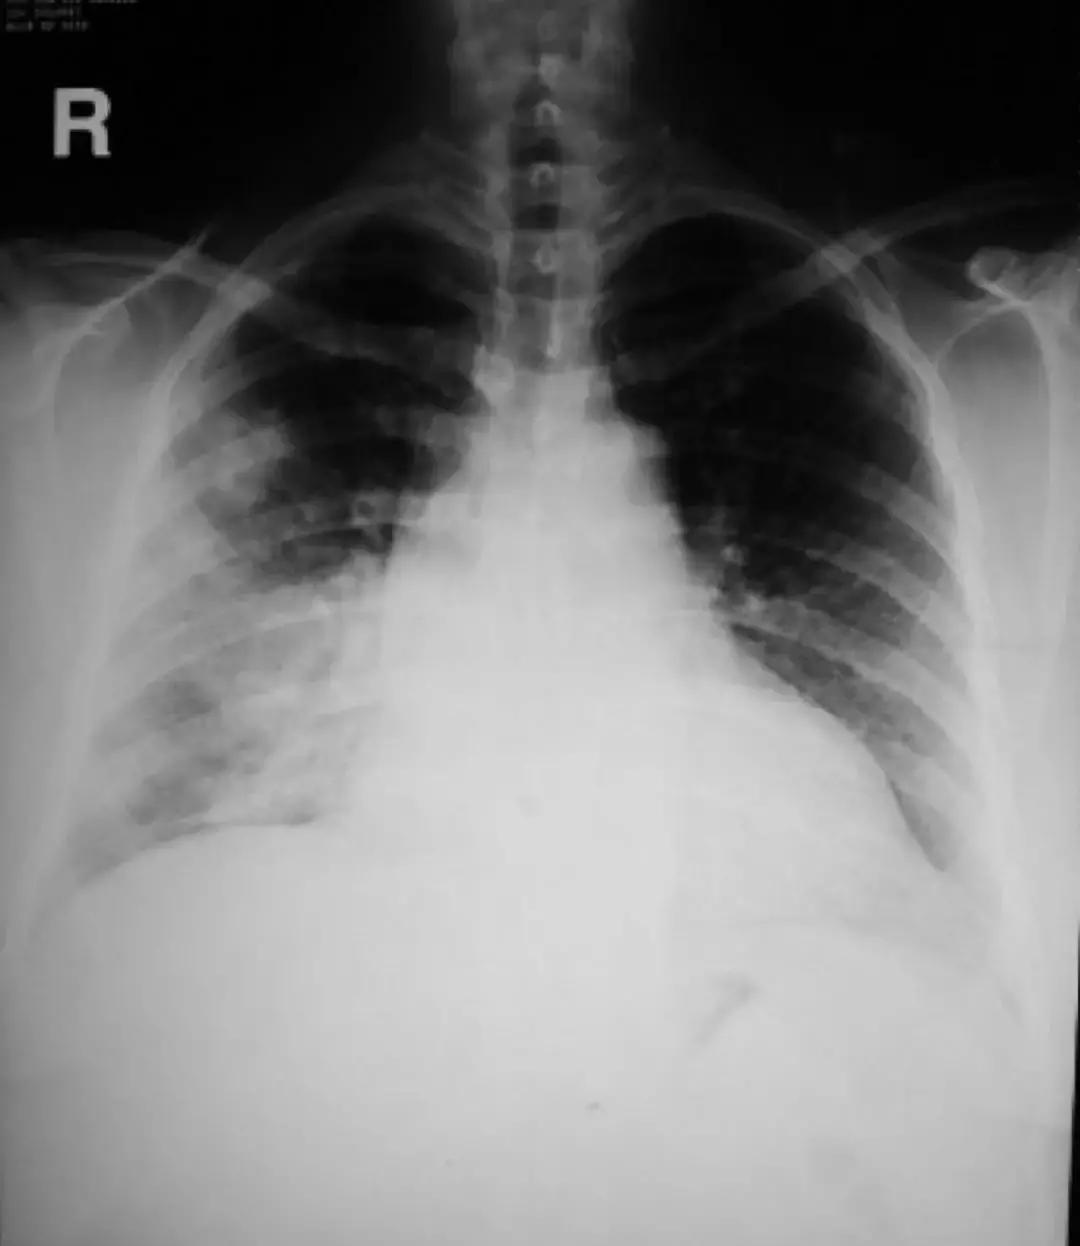

对于肺部感染的诊治来说,细菌、病人、抗菌药物、医生……到底谁是赢家?一切皆有可能!所谓「谍影重重」,就是胸部CT上的各种影像,一提到胸部CT,大家最容易想到的就是下图中在临床上最常见的影像学图像:

这种影像绝大部分是肺炎,在基层医院肺炎最常见的治疗方法是抗菌药物、皮质激素、维生素。